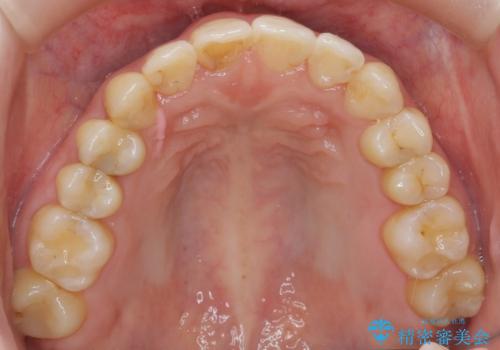

犬歯のねじれ 上の歯が引っ込んでいる

- 前歯の並びを気にして来院。

インビザラインで、上の前歯をやすり掛けして並べました。

途中妊娠、出産を挟み、患者様がアライナーがつけられない時期もあって治療自体は延長しました。